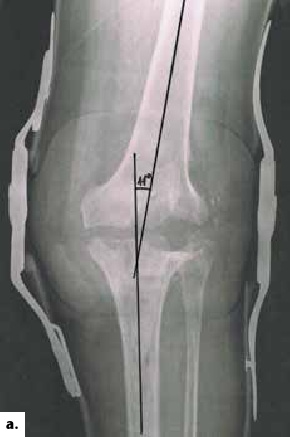

Als Osteosynthesematerial dient ein Fixateur externe, der sich auf die beiden knienahen Drittel erstreckt (Abb. 2a u. b). Der Durchbau dauert bis zu einem Jahr. Nach 3 bis 4 Monaten kann der Fixateur durch eine hintere Schalenorthese mit beweglicher Sandale ersetzt werden. Damit lassen sich die ersten Schritte unternehmen. Nachträglich lassen sich die beiden Knochenstümpfe durch eine Arthrodese mit einem Marknagel stabilisieren 5.